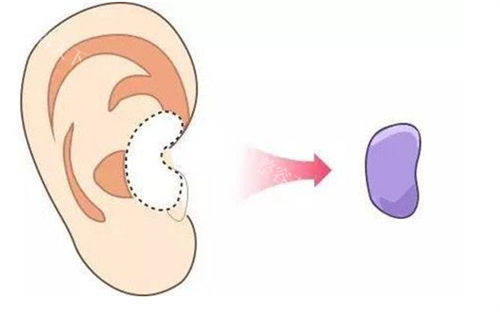

半肋软骨技术的核心优势在于“材料源于自身,塑形更贴合原生条件”。取用肋软骨中的柔性部分雕刻鼻尖支架,既能避免假体的异物感,又能精细控制鼻尖旋转度、延长鼻小柱。